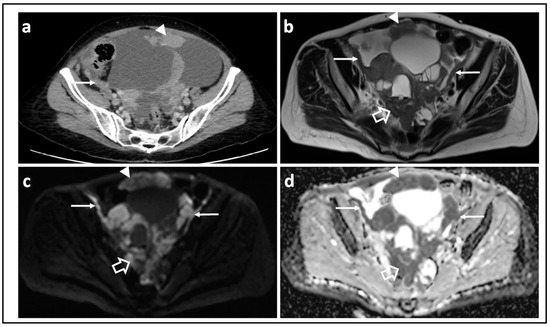

The sensitivity of the DW-MRI sequence to diffusion is characterized by its b-value (a combination of gradient pulse amplitude, the time for which the gradients are applied, and the time that elapses between their application). These parameters can be adjusted to alter the sensitivity of the sequence to diffusion. The higher the b-value, the more sensitive an image is to the effects of diffusion. An optimal high b-value to image peritoneal metastases from ovarian cancer is around 1000 s/mm2 [18] (Figure 1). Microcirculation of blood in the capillary bed (perfusion) means that perfusion contributes to the loss in signal on a DW-MRI image. Fortunately, the movement of water due to microcirculation has a diffusivity 10 times larger than true diffusion [19] and are normally evident when b-values are below 100 s/mm2 [20]. A range of b-values between 100 and 1000 s/mm2 are ideal for delineating metastatic ovarian cancer [21].

Figure 1.

Peritoneal metastases in high grade serous ovarian cancer showing increasing lesion conspicuity with increasing b-value: T2-W (a) and DW-MRI at b-values of 0 s/mm2 (b), 100 s/mm2 (c), 500 s/mm2 (d), and 900 s/mm2 (e). The irregular metastatic deposits on the surface of the bowel and in the mesentery (arrows) show diffusion restriction. They increase in conspicuity and contrast as diffusion weighting increases because they retain signal while signal from adjacent normal tissues diffuses away.